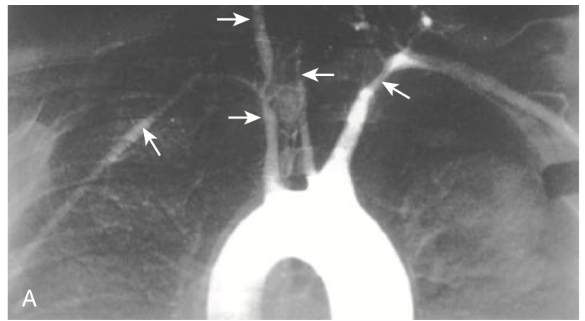

Takayasu disease

aortic arch angiogram showing reduced flow of contrast material into the great vessels and narrowing of the brachiocephalic, carotid and subclavian arteries